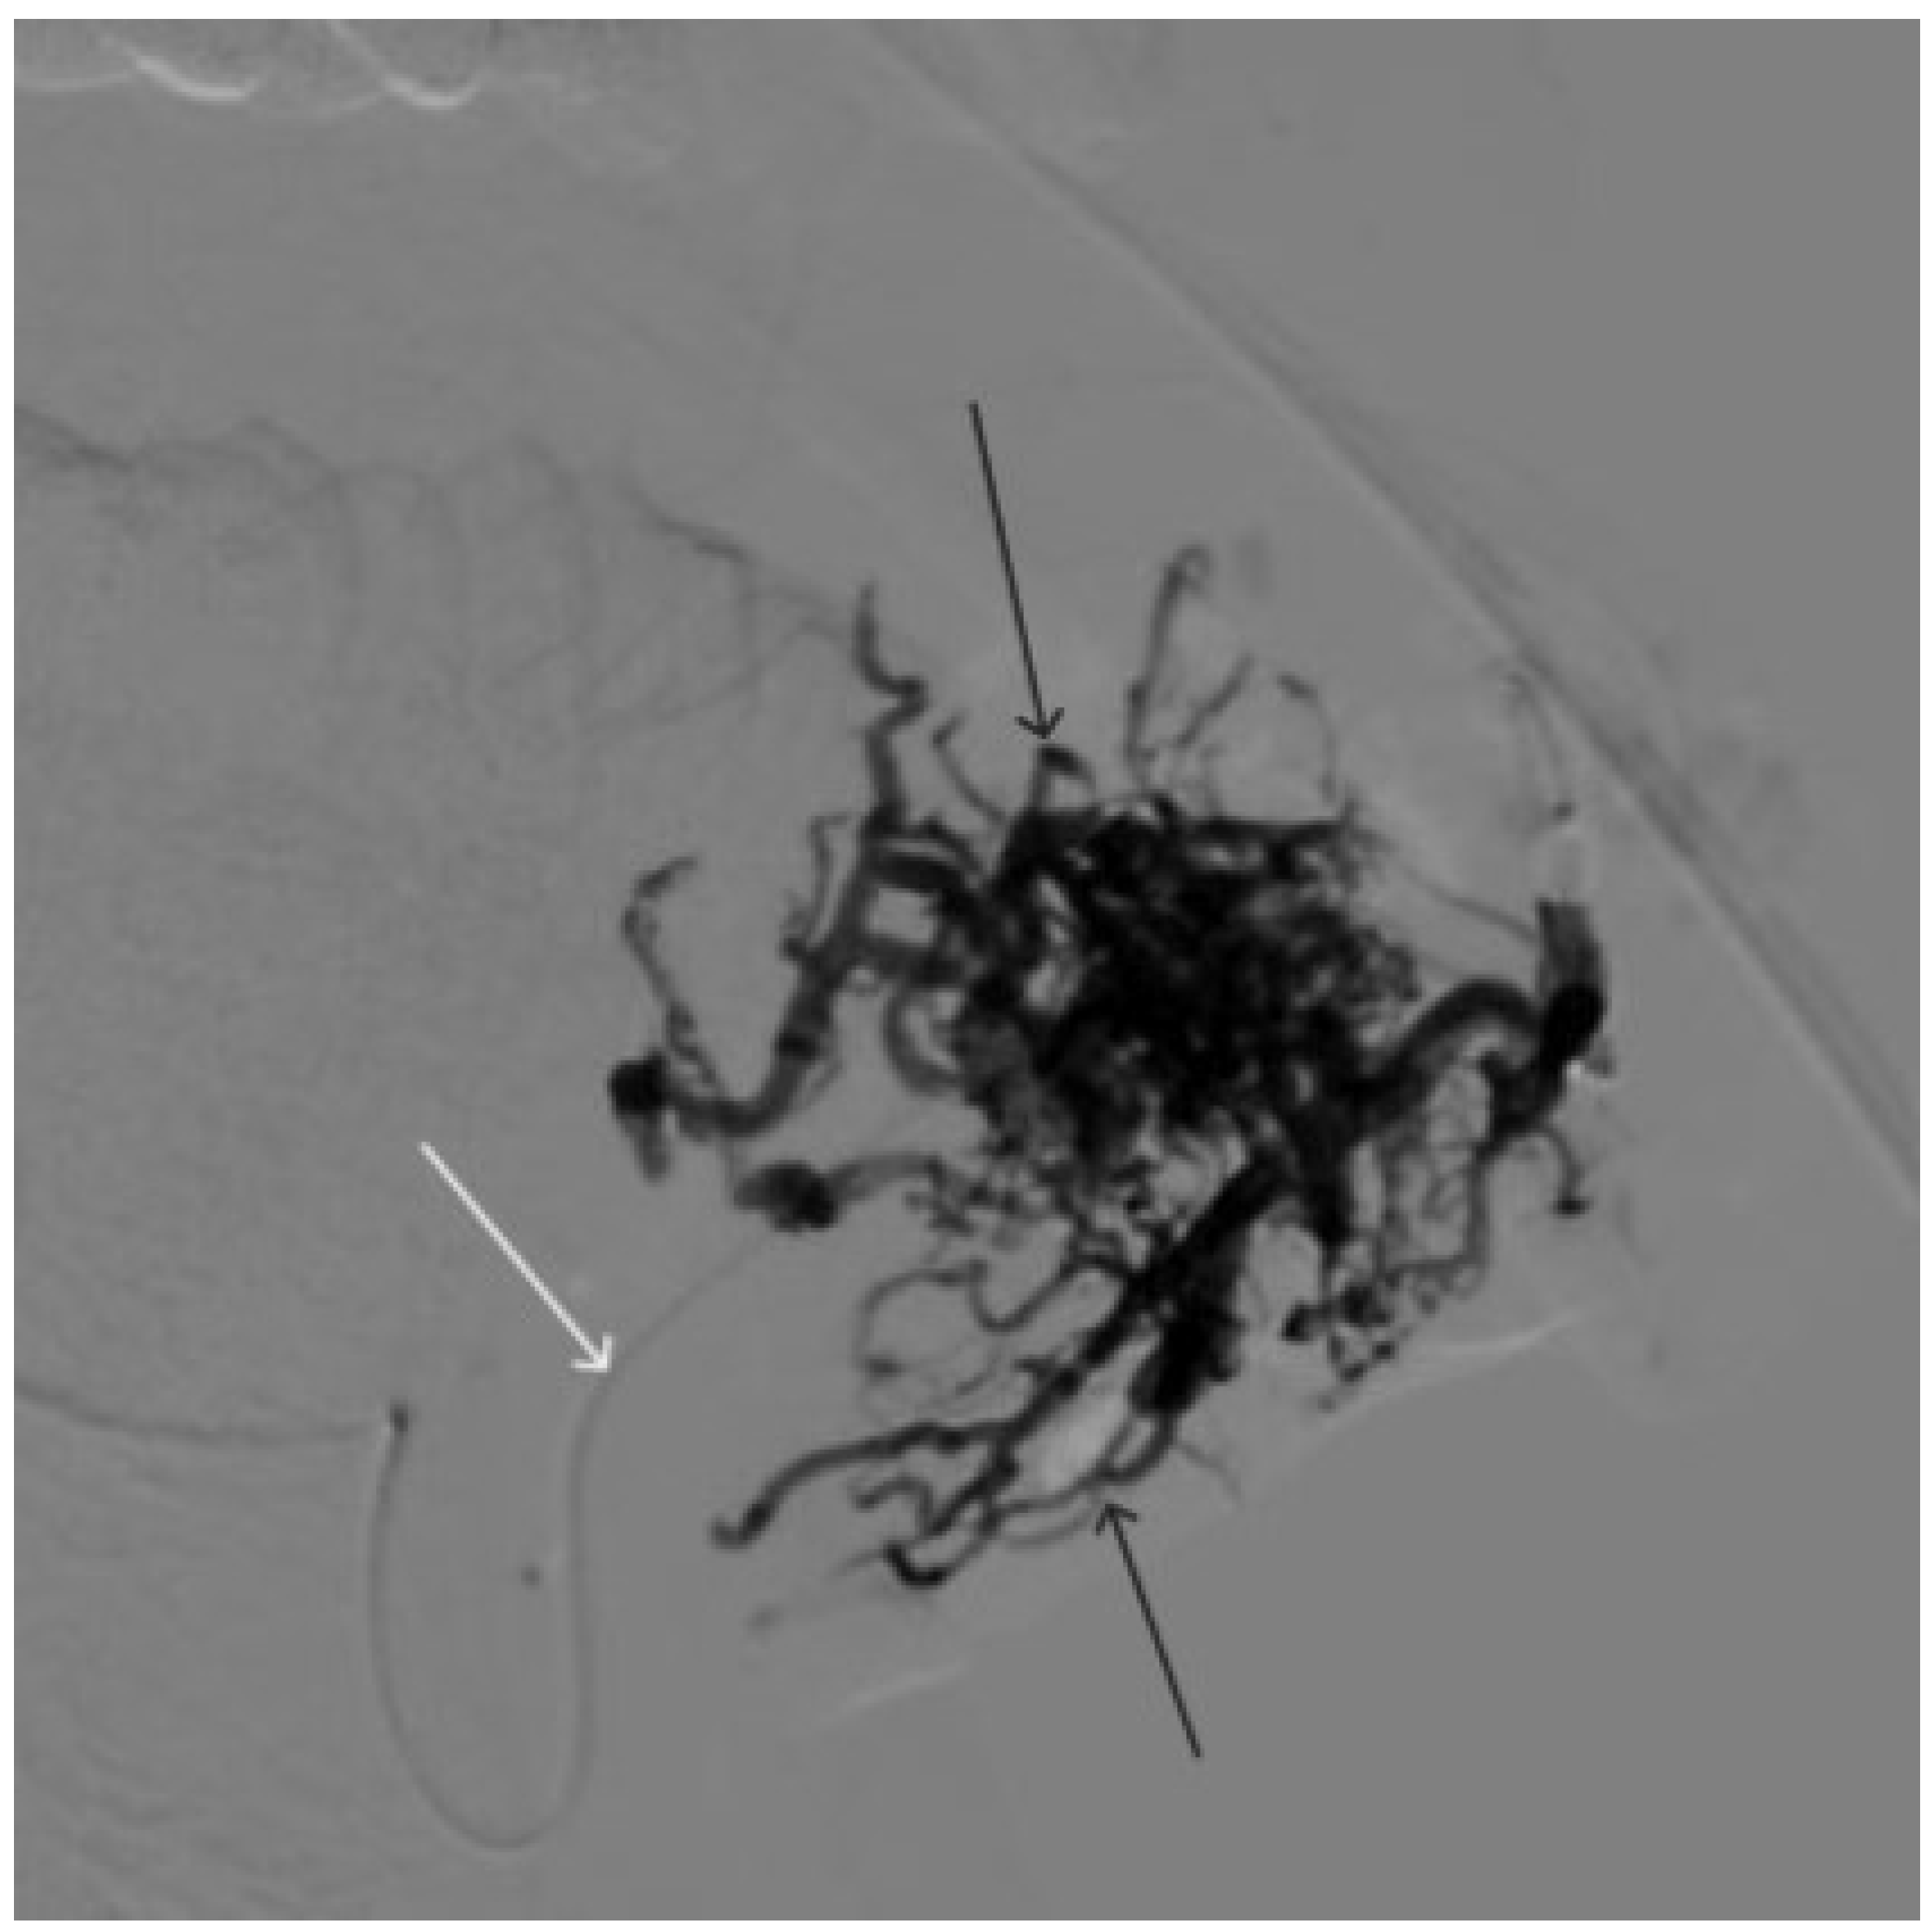

Figure 4. The process of introducing Onyx-18 into the AVM of the lower lip (the white arrow indicates the microcatheter, the black arrow indicates the spread of embolizate along the vascular network of the formation).